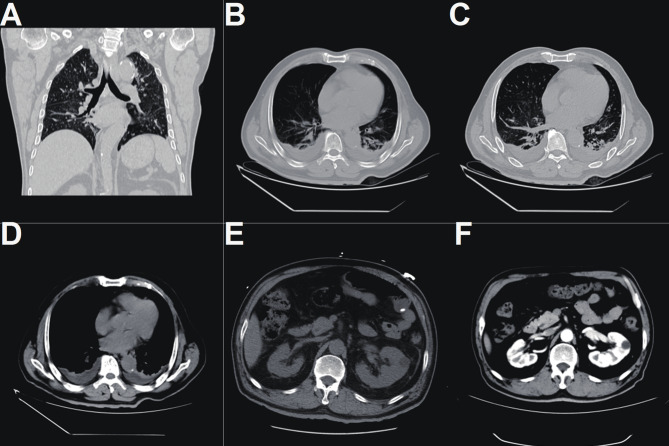

A thorough physical examination revealed abdominal distension and mild tenderness in the lower left abdomen, with no other abnormal findings. Imaging studies (chest and abdominal CT) showed: (1) Bilateral renal cysts, mild hydronephrosis and left ureteral dilation, and slight thickening of the bladder wall—indicative of postoperative changes from bladder tumor surgery; (2) Bilateral pneumonia, pleural effusion, and collapse of the lower lobes of both lungs; (3) A low-density lesion in the left hepatic lobe; and a left inguinal hernia (Fig. 1).

Fig. 1.

Chest CT revealed bilateral pulmonary inflammation with pleural effusion on both sides and atelectasis in the lower lobes (A-D).Abdominal CT demonstrated a low-density lesion in the lateral segment of the left hepatic lobe, bilateral renal cysts, and mild hydronephrosis of both renal pelves and the left ureter. The bladder wall was mildly thickened, suggestive of postoperative changes following bladder tumor resection. Additionally, a left inguinal hernia was noted (E-F)